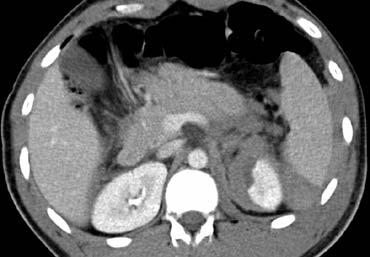

Hình ảnh bên trái của bệnh nhân nam 44 tuổi nhảy từ độ cao 12 mét xuống mặt bê tông trong một vụ tự tử.

Tiền sử điều trị trầm cảm.

Huyết áp 90/54. Da xanh tái, vã mồ hôi, lú lẫn.

Không có chấn thương đầu. Bầm tím vùng ngực và bụng.

Bụng chướng. Khung chậu mất vững rõ rệt.

Đái máu đại thể.

Cuộn qua các hình ảnh bên trái và mô tả các dấu hiệu.

Các dấu hiệu bao gồm:

- Giảm tưới máu lách (mũi tên vàng).

- Nhiều vùng thoát thuốc cản quang (mũi tên xanh lá).

- Tràu máu ổ bụng và tràn khí ổ bụng.

- Nhiều đoạn ruột có thành dày lan tỏa (mũi tên xanh dương).

Các câu hỏi đặt ra đối với bệnh nhân này:

- Tràn khí ổ bụng có phải là dấu hiệu chẩn đoán xác định tổn thương ruột xuyên thành không?

- Dấu hiệu thành ruột non dày lan tỏa gợi ý điều gì?

- Với cơ chế giảm tốc theo chiều dọc, tổn thương ruột có khả năng xảy ra nhiều nhất ở vị trí nào?

Thực tế, các dấu hiệu thường gặp nhất trong tổn thương ruột non là những dấu hiệu không đặc hiệu như thành ruột dày và dịch tự do trong ổ phúc mạc không rõ nguyên nhân.

Ở bệnh nhân đã thảo luận, tình trạng thành ruột dày lan tỏa chỉ là hậu quả của giảm tưới máu hay còn gọi là “ruột sốc” do chảy máu đang tiến triển.

Tổn thương trực tiếp thành ruột thường biểu hiện bằng dày thành khu trú và phần lớn là tổn thương không xuyên thành.